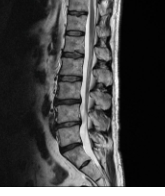

추간판 탈출증은 척추의 디스크가 손상되어 주변의 신경을 압박하는 상태를 말합니다. 추간판 탈출증은 나이가 들면서 디스크가 닳거나, 과도한 운동이나 사고 등으로 인해 발생할 수 있습니다. 추간판 탈출증은 허리뿐만 아니라 다리나 엉덩이에도 통증이 전이되며, 감각이나 운동 장애가 생길 수 있습니다. 추간판 탈출증은 보통 약물 치료나 물리 치료로 호전될 수 있지만, 심한 경우에는 수술이 필요할 수 있습니다.

허리디스크는 척추뼈 사이에 있는 디스크가 손상되어 신경을 압박하는 질환입니다. 디스크는 척추뼈 사이의 충격을 흡수하고 척추의 움직임을 부드럽게 해주는 역할을 하는데, 이 디스크가 손상되면 신경을 압박하여 통증, 마비, 감각 이상 등의 증상이 나타납니다. 허리디스크는 흔히 40~50대 중년층에서 발생하지만, 젊은 나이에도 발생할 수 있습니다. 원인은 다양하지만 가장 흔한 원인은 갑자기 무거운 것을 들거나 허리를 삐끗하는 등의 외상입니다.

허리디스크의 대표적인 증상은 요통과 방사통입니다. 요통은 영향을 받은 디스크 부위에서 발생하며 둔한 통증, 날카로운 통증 또는 지속적인 불편감으로 나타날 수 있습니다. 통증의 강도는 다양할 수 있으며 영향을 받은 디스크에 압력을 가하는 움직임으로 악화될 수 있습니다. 방사통은 일반적으로 영향을 받은 신경의 경로를 따라 엉덩이, 허벅지, 다리로 이동합니다. 통증은 해당 부위의 따끔거림, 무감각 또는 바늘로 찌르는 듯한 감각을 동반할 수 있습니다.

허리디스크의 다른 증상으로는 근육 약화와 신경 압박이 있습니다. 근육 약화는 허리디스크로 인해 해당 부위의 근육이 약해질 수 있습니다. 이러한 근력 약화는 허리디스크의 위치에 따라 다리나 팔에서 눈에 띄게 나타날 수 있습니다. 이는 조정력, 안정성, 특정 동작이나 작업 수행 능력에 영향을 미칠 수 있습니다. 신경 압박은 허리디스크가 주변 척추 신경을 압박하여 신경 압박 또는 충돌과 같은 상태를 유발할 수 있습니다. 이로 인해 바늘로 쏘이는 듯한 통증, 찌릿한 통증 또는 영향을 받는 신경 경로를 따라 감각 상실과 같은 증상이 나타날 수 있습니다.

허리디스크의 증상은 질환의 위치와 심각도에 따라 다르게 나타날 수 있으므로 정확한 진단과 치료가 필요합니다. 만약 위와 같은 증상이 있다면 병원에서 검사를 받아보시기 바랍니다. 허리디스크는 조기에 발견하고 적절한 치료를 받으면 자연 치유가 가능한 경우도 있습니다. 허리디스크를 예방하고 관리하기 위해서는 잘못된 자세와 생활 습관을 고치고, 체중 관리와 금연을 하며, 허리에 좋은 운동과 스트레칭을 꾸준히 하는 것이 중요합니다.